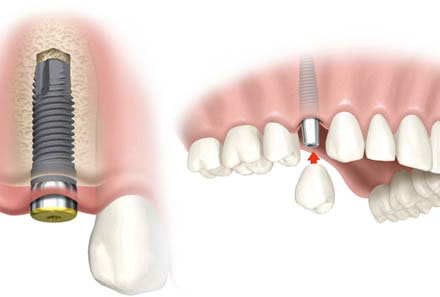

sostituire singoli denti, senza coinvolgere i denti vicini, così come avveniva in passato quando non esisteva alternativa alla realizzazione di un Ponte.

Gli impianti da noi utilizzati sono a forma di vite, hanno un diametro da 3,5 a 6,0 mm e una lunghezza da 5 a 15 mm, approssimativamente, quindi, la dimensione di una radice naturale.